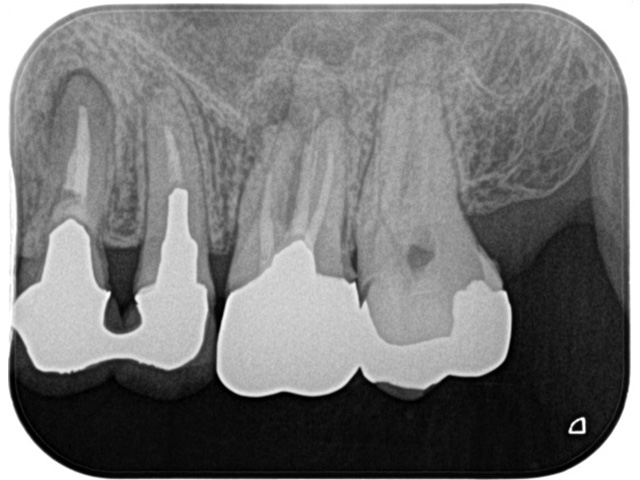

Before

| 主訴 | 右上の奥歯が咬むと痛む |

|---|---|

| 治療内容 | 右上第一大臼歯、第二大臼歯の精密根管治療 |

| 治療回数・期間 | 3回(3週間) |

| 費用 | 保険適応 |

| リスク・副作用 | 根管治療は術前の精密な診査診断および無菌環境下での治療によって成功率は高まってきましたが治療の成否を決める多くの要素があるため、根管治療がなされた後も再治療や外科処置、抜歯となる可能性が少なからずあります。また治療中には器具の破折や穿孔、修復物の損傷、歯の破折、術中・術後の痛みや腫れが生じることが稀にあります。根尖病変(再感染)を防ぐには適合の良好な補綴物を作製することや定期的なかみ合わせのチェックが必要です。 |